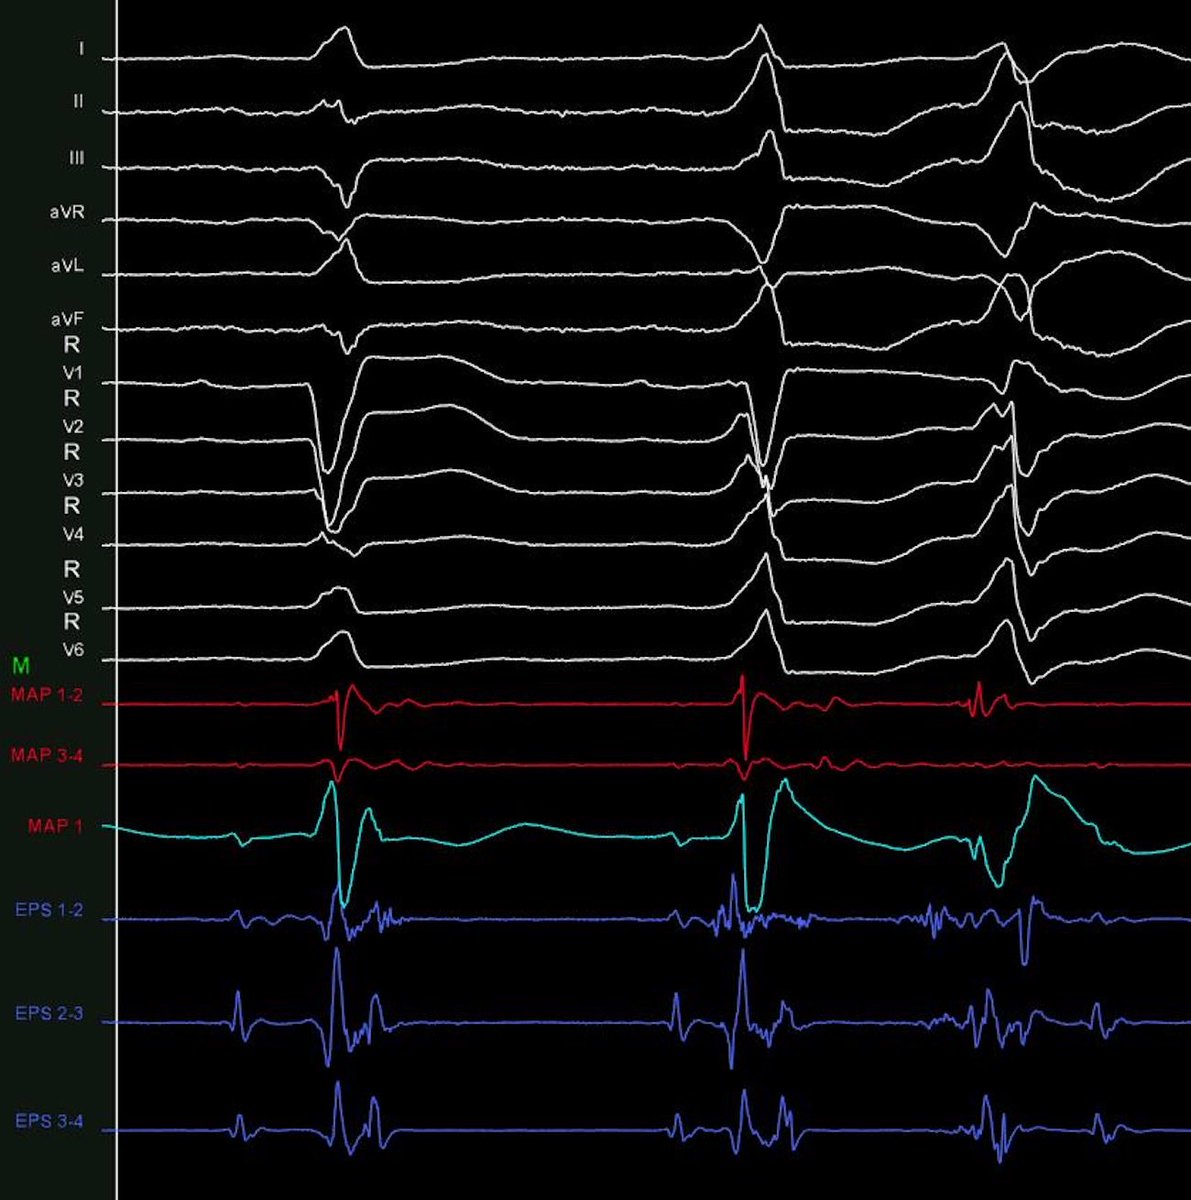

75 y.o.F. chagas CM, LVEF 44% and VT despite amiodarone. Detailing scar physiology in Chagas disease with omnipolar EGM. #ablateVT @fcardioinfantil @drluissaenz @DrFerminGarcia @andresenriqueza @Dr_Santangeli @DrRoderickTung @CarinaHardy4